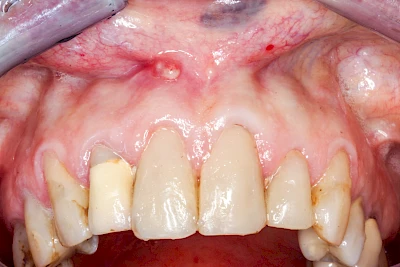

Sonderform: Fistel

Bei einer Fistel hat sich meist eine Entzündung (manchmal auch Erreger selbst) z. B. aufgrund von Karies oder aufgrund eines Unfalls über den Zahnnerv und die Wurzelspitze (Apex) in den umliegenden Knochen ausgebreitet (apikale Parodontitis) und schnell einen Weg durch den umgebenden Knochen und die aufliegende Schleimhaut in die Mundhöhle gebahnt.

Fisteln sind in der Regel nicht schmerzhaft und fallen häufig als kleine Öffnung weiter entfernt vom Zahnfleisch nahe der Umschlagfalte auf. Aus der Fistelöffnung entleert sich spontan gelbliches Sekret (Eiter) oder es lässt sich mit dem Finger ausstreichen. Manchmal beschreiben die betroffenen Menschen immer wieder einen komischen Geschmack im Mund.

Im fortgeschrittenen Stadium kann die Schleimhaut sich weiter zurückgezogen haben und die Wurzelspitze sichtbar sein. In der Regel treten bei Fisteln keine Schwellungen auf, weil sich die Entzündung nicht im Gewebe ausbreitet.

Bei Fisteln sollte zeitnah der Zahnarzt kontaktiert werden. Treten Fisteln im Zusammenhang mit Schwellungen auf, ist sofort der Zahnarzt zu kontaktieren. Ist der Zahnarzt nicht zu erreichen und es verschlechtert sich der Allgemeinzustand (z. B. Fieber) sollte der Notarzt gerufen werden.